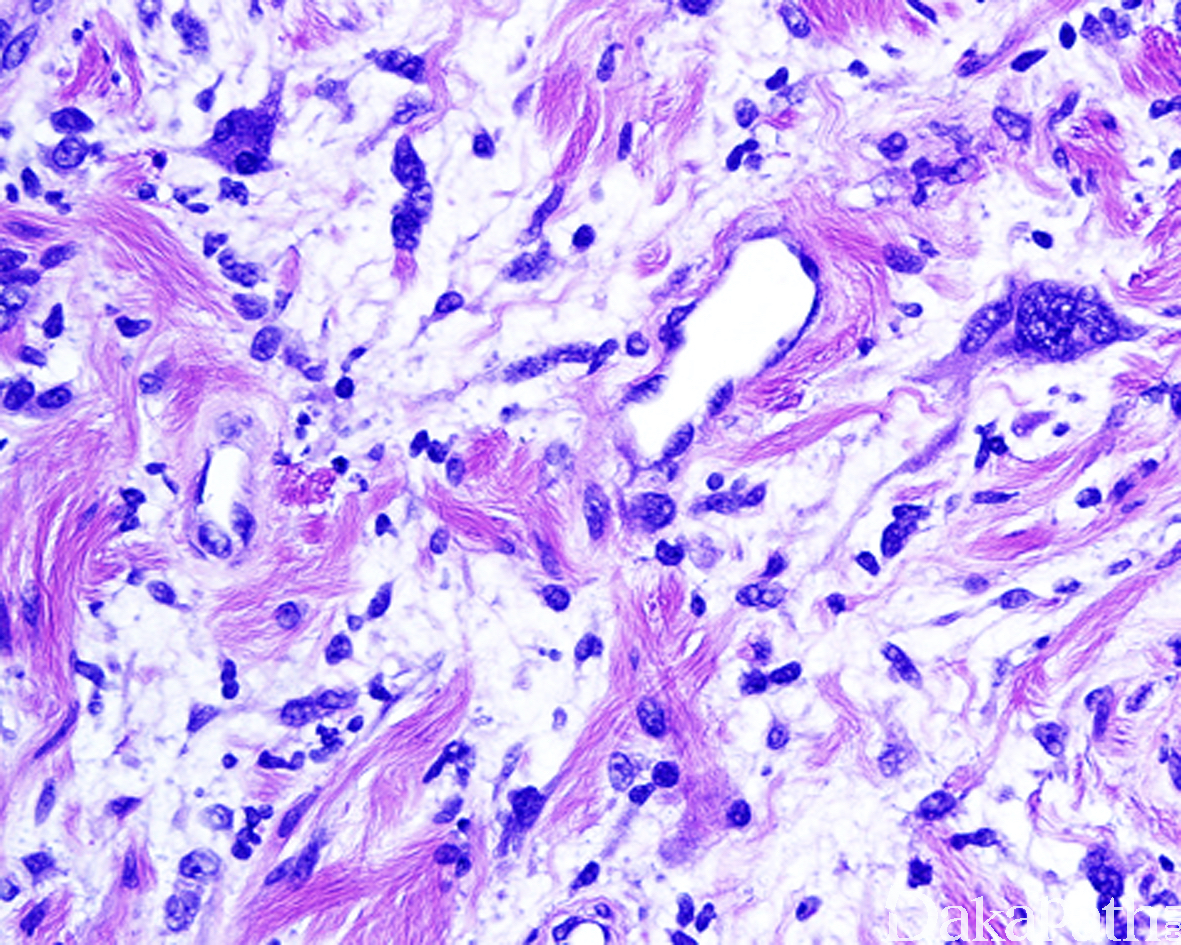

在神经纤维瘤形态学结构基础上,出现散在、核大、染色质呈污浊状,核仁不明显,核内可见胞质性的包涵体的核异型细胞,无核分裂像。

S-100. MBP、XIIIa、CD34 阳性,可见 EMA 阳性神经束膜细胞,NF 阳性的轴突成分;P53 阴性,Ki67 增殖指数低,H3K27me3 无表达丢失;多数病例无表达缺失,少数可出现表达缺失。